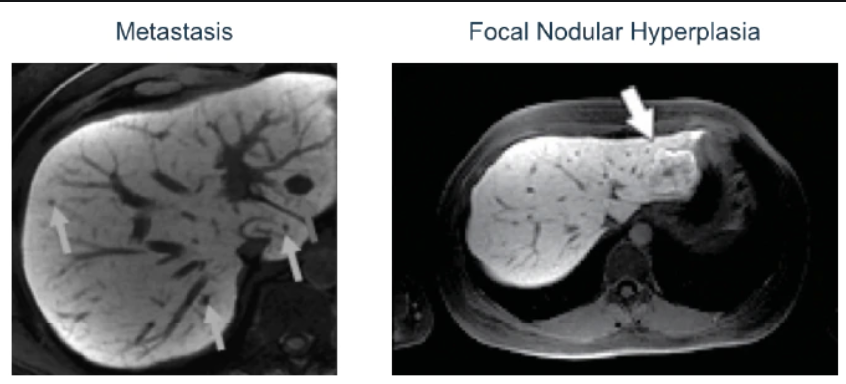

DDx multiple tiny hepatic hypoattenuating lesions

Hepatic infection: abscess

Ix: CT-1

MR-4

Ix: CT: ring-enhancing lesion

MR: T2 central hyperintensity, irregular wall that enhances late, perilesional enhancement.